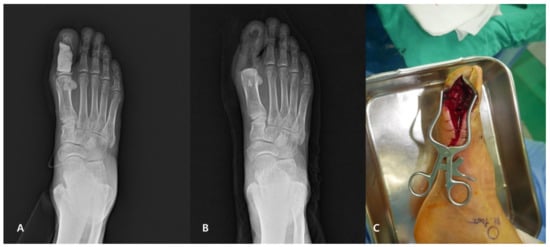

2.3. Surgical Technique